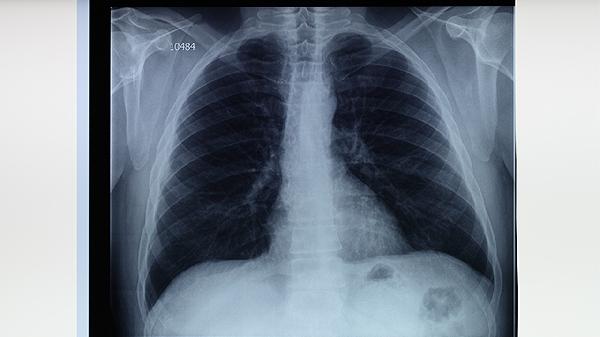

肺结核患者应遵医嘱完成6-8个月规范治疗,治疗期间保持均衡饮食,适当补充优质蛋白和维生素A/C/D。注意隔离防护,咳嗽时掩住口鼻,定期开窗通风。完成治疗后仍需定期复查胸部影像学,监测病情变化。